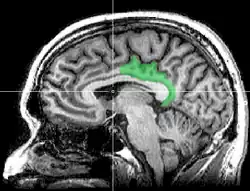

Cortex cingulaire postérieur

Le cortex cingulaire postérieur (CCP) est, dans le cerveau, une zone à l'arrière du cortex cingulaire ressemblant à une ceinture entourant le corps calleux.

- cortex cingulaire postérieur CCP, avec le même nom mais limité aux aires 23 et 31

- cortex rétrosplénial CRS, regroupant les aires 29 et 30. Il entoure directement le splenium du corps calleux.

Pour éviter les confusions, Brent A. Vogt appelle l'ensemble formé par le cortex cingulaire postérieur (CCP) et le cortex rétrosplénial (CRS), le gyrus cingulaire postérieur.